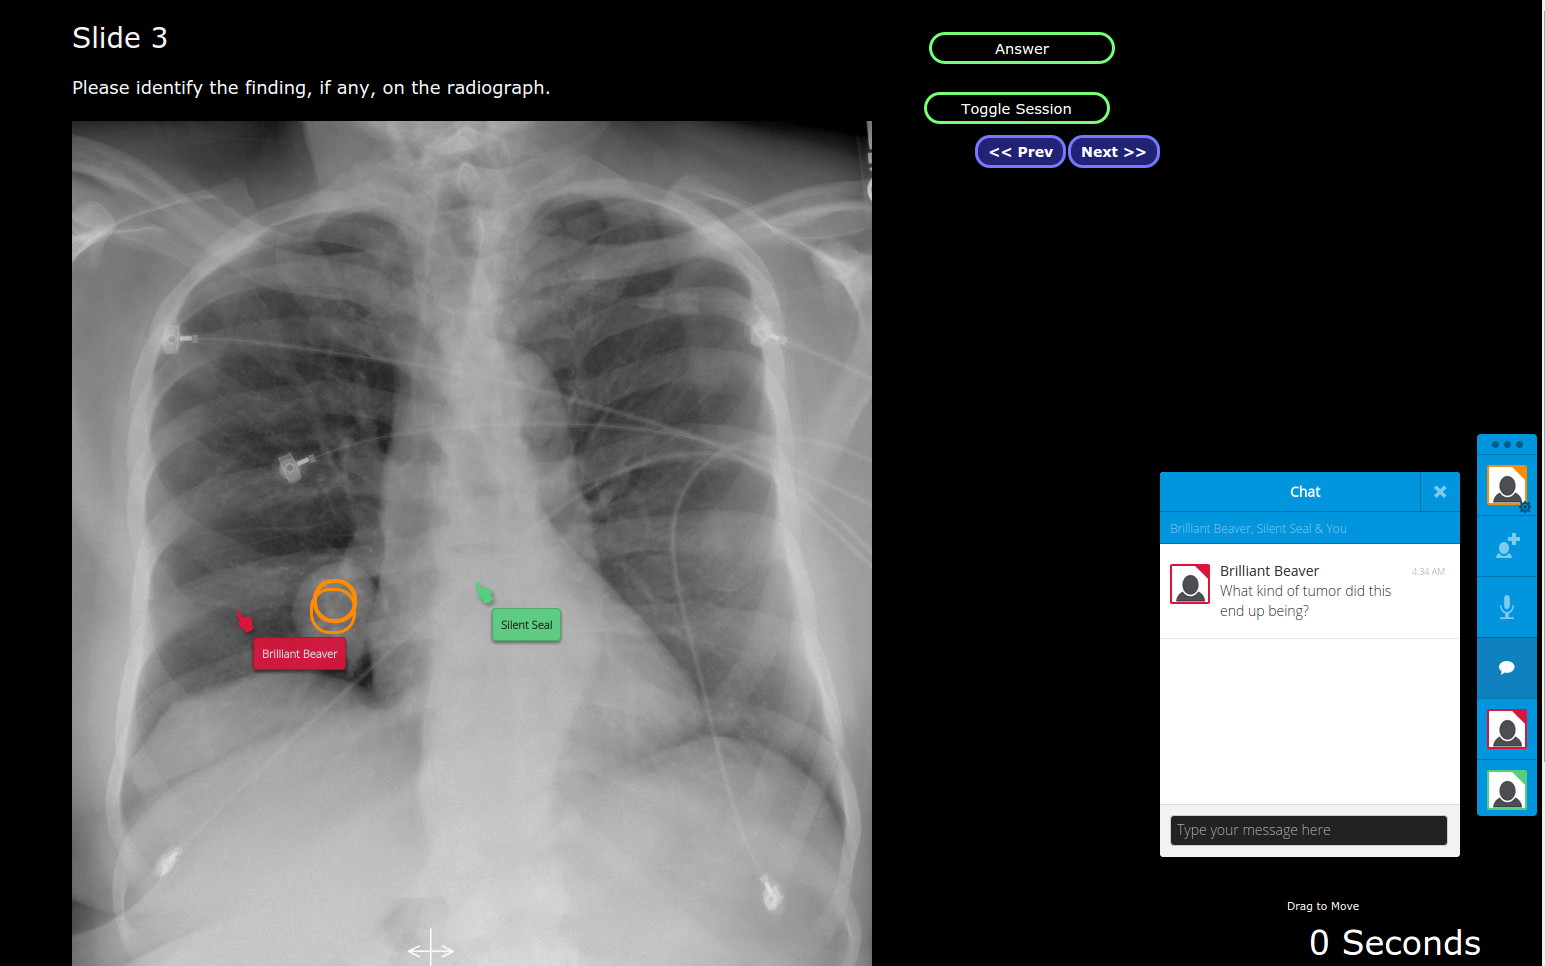

At scientific conferences the situation is worse - a lecture hall has hundreds of seats, so when the speaker asks the audience a question "do you guys see anything wrong with this X-ray? Where is the disease?" There is no participation - the speaker has a laser pointer, the audience has nothing.

The entire careers of radiologists and other imaging processionals rely on being able to communicate clearly using images. I created SharedDx to allow real-time collaborative discussion about medical imaging both in a real-life conference setting and in a virtual conference (e.g. conference call).

2. Everyone in the audience can jump into the presentation slide using their phone/tablets and point at abnormalities and pose questions to the speaker through a chat window.